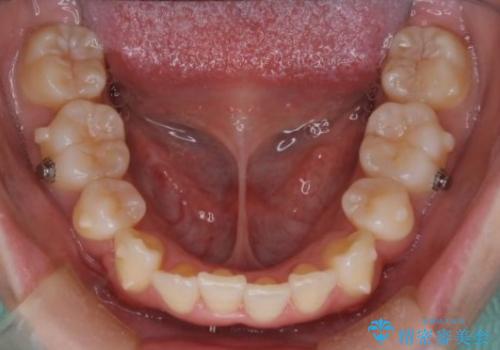

治療途中に出産やコロナがあり、2年ほど来院途絶えてしまいましたが、無事治療を終えることができ満足していただきました。

来院が途中途絶えたこともあり、4年ぐらい期間がかかりましたが、インビザラインだけで治療を終えることができました。